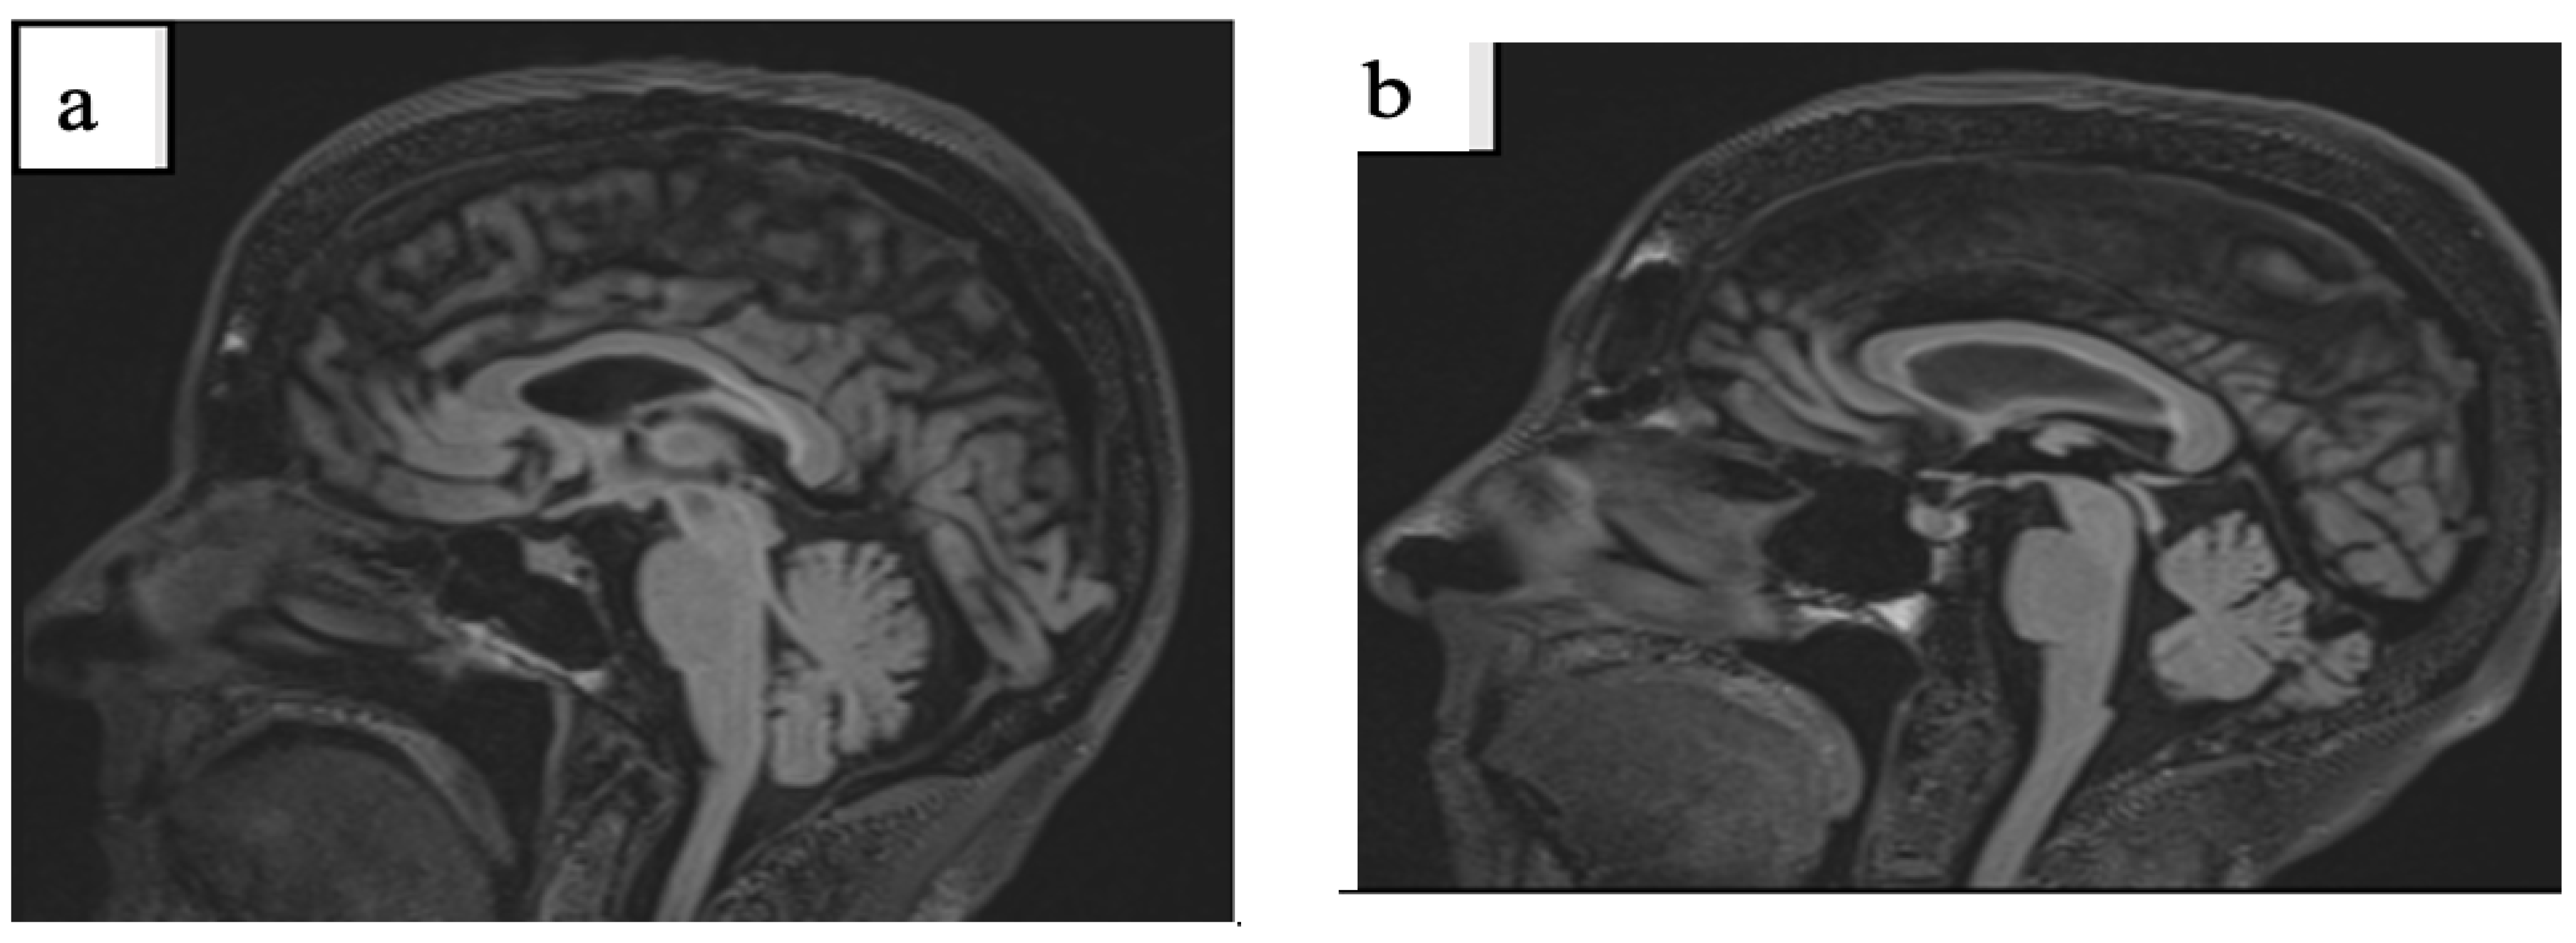

3.1. Case 1

3.2. Case 2